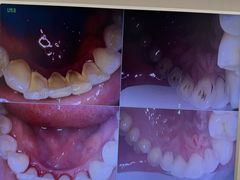

• 圣贝口腔医院(高新院区)

• -圣贝口腔医院(高新院区)

Vronsky | 24-09-21

leven | 24-09-21

小妍爱吃饭 | 24-09-21